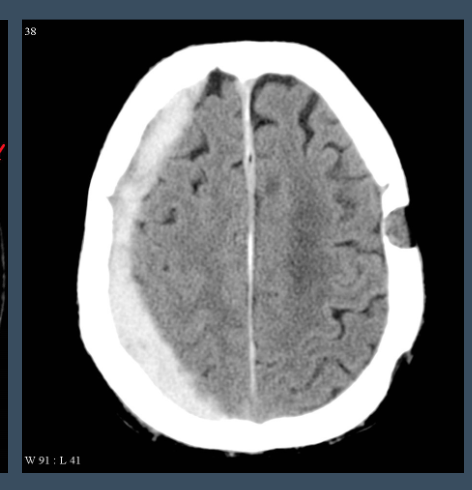

What type of injury is shown in the provided image?

Subdural hemorrhage (concave/crescent-shaped)

Elderly; EtOH abuse

YES - surgery idicated